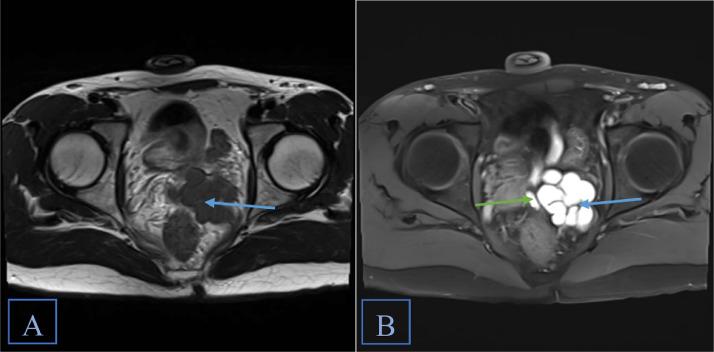

Zinner syndrome comprises a triad of unilateral renal agenesis, ipsilateral seminal vesicle cyst, and ejaculatory duct obstruction, which can be accompanied by additional abnormalities of the genitourinary tract in some cases. Patients may be asymptomatic or present with urinary, reproductive, and/or local pain symptoms. Diagnosis is most commonly achieved via MRI. Here, we present the case of an 18-year-old male previously diagnosed with unilateral renal agenesis, who presented with testicular and penile pain, along with urinary urgency and frequency. MRI of the abdomen and pelvis revealed all three components of Zinner syndrome as well as an ectopic ureter emptying into the seminal vesicle. Our case adds to the existing limited literature on this rare syndrome and broadens the understanding of how this syndrome can present both clinically and radiologically.

齐纳综合征包括单侧肾缺如、同侧精囊囊肿和射精管梗阻三联征,某些情况下可伴有泌尿生殖道的其他异常。患者可能无症状,或出现泌尿系统、生殖系统和/或局部疼痛症状。诊断最常用的方法是磁共振成像(MRI)。在此,我们报告一例18岁男性病例,该患者此前被诊断为单侧肾缺如,现出现睾丸和阴茎疼痛,伴有尿急和尿频。腹部和盆腔的MRI显示了齐纳综合征的所有三个组成部分,以及一条异位输尿管排入精囊。我们的病例补充了关于这种罕见综合征的现有有限文献,并拓宽了对该综合征在临床和影像学上表现的认识。